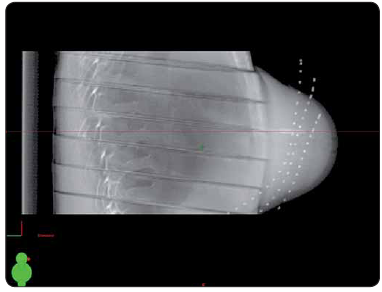

Po lokalizaci cílového objemu se na BRT sále zavádí do prsu ozařovací katetry pomocí dutých jehel. Těmito jehlami jsou protaženy ozařovací katetry, které slouží k zavedení Ir (iridiového) zdroje pro ozáření. U pacientky je provedeno plánovací CT vyšetření se zavedenými katetry. Pro správnou lokalizaci těchto katetrů je nutné je při CT vyšetření zviditelnit. K tomu slouží rentgenkontrastní markery, které se před CT vyšetřením vloží do katetrů, a umožňují tak správně zakreslit průběh katetrů pro potřeby plánování. Po změně výrobního programu bylo možné u dodavatelské firmy zakoupit pouze nové markery, které však již neodpovídaly původně používaným markerům. Nové markery mají speciální provedení, bohužel však nemají stejnou tloušťku v celé délce průběhu, proto nejsou v některých CT řezech vidět, a marker tak v nich nemůže být zcela jednoznačně identifikován.

Provedli jsme několik zkušebních CT vyšetření s různými tloušťkami řezu s pomocí speciálního antropomorfního fantomu, do kterého jsme umístili zkušební katetry i s novými markery. Z každého takového souboru CT řezů byla v plánovacím systému vytvořena 3D rekonstrukce a následně jsme se pokoušeli správně identifikovat jednotlivé katetry. Nejpřesnější zobrazení průběhu katetrů ve fantomu je možné při tloušťce řezu 1 mm v sekvenčním režimu. Řezy tloušťky 3 mm se jeví jako nedostačující. Pro CT vyšetření u pacientky jsme zvolili tloušťku řezů 2 mm.